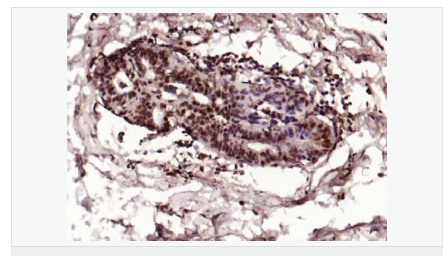

image.png